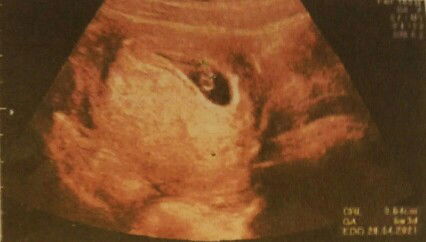

Các mom ơi cho e hỏi thai được 6 tuần 4 ngày như này là bình thường đúng ko ạ